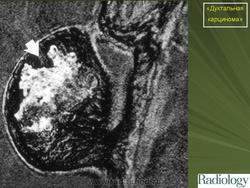

Инвазивная (или инфильтрирующая) протоковая карцинома – это наиболее часто встречающаяся форма рака молочной железы. Она составляет около 80 % из всех форм. В отличие от протоковой карциномы in situ, инвазивная карцинома характеризуется тем, что раковый процесс уже вышел за пределы молочного протока и распространяется на нормальные ткани молочной железы. Характерной особенностью инвазивной протоковой карциномы является очень твёрдая припухлость с неровными краями, которая спаяна с окружающим тканям. Сосок молочной железы или кожа вокруг него может быть втянута.

Часто на маммограммах в области опухоли выявляются микрокальцинаты, что связано с том, что в опухоли происходит омертвление ее клеток (некроз), которые в последствие пропитываются солями кальция. Опухоль при инвазивной карциноме может быть различных размеров, и у клеток может быть различное время деления, так что некоторые клетки растут быстрее других.